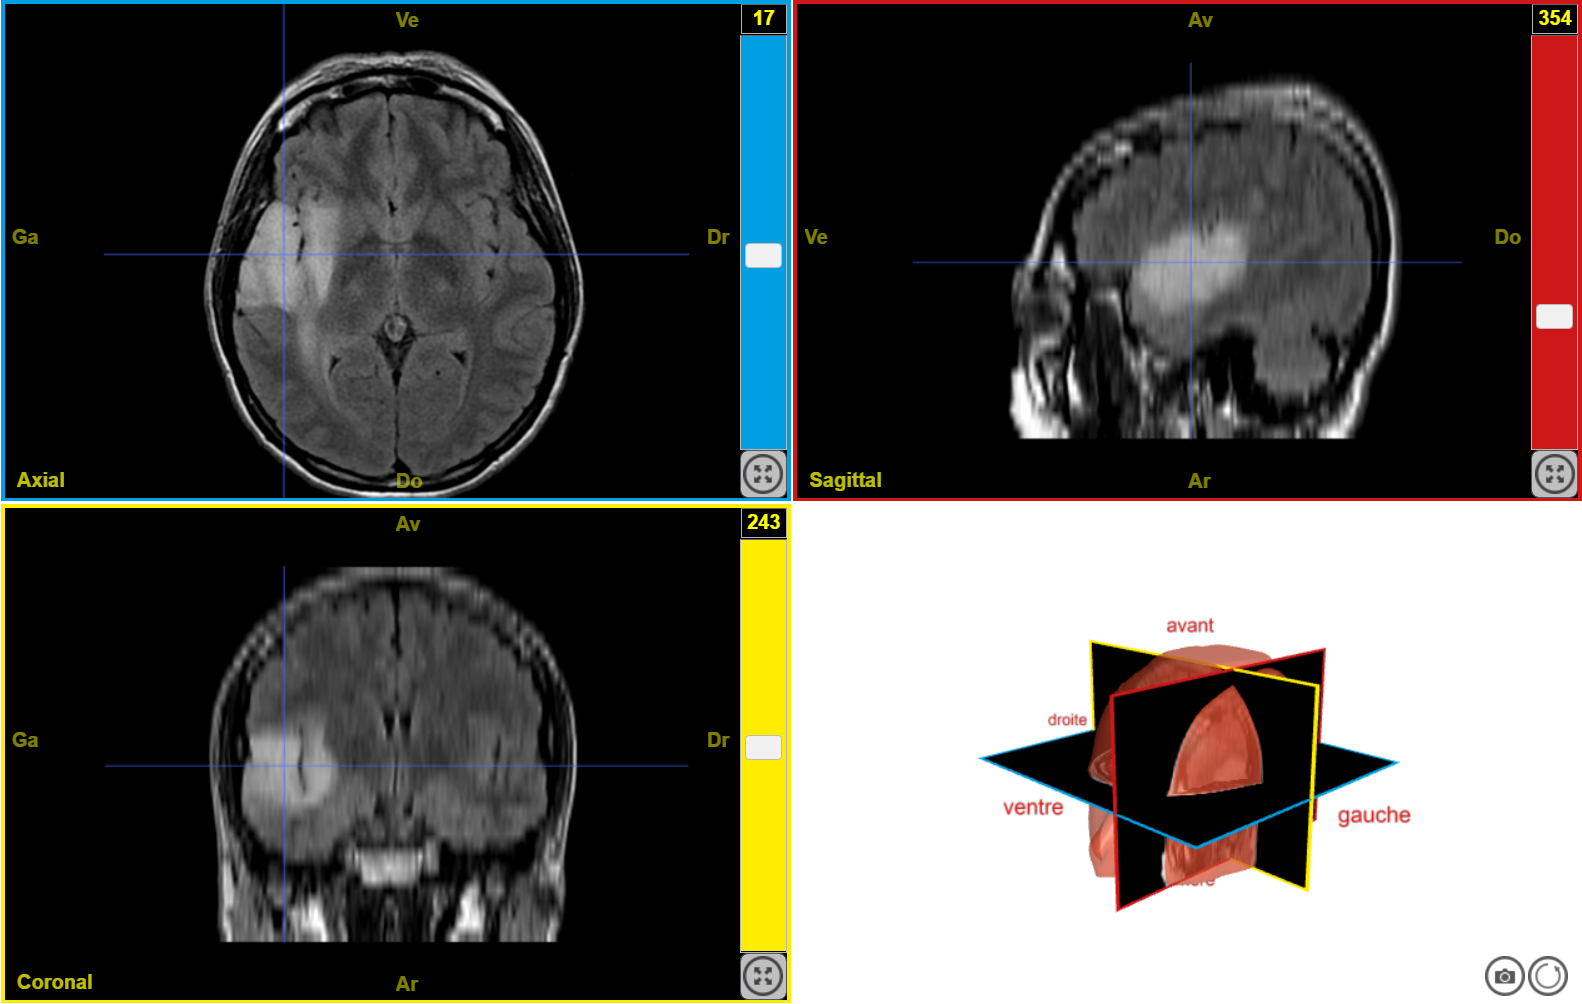

IRM tumeur T2 n1